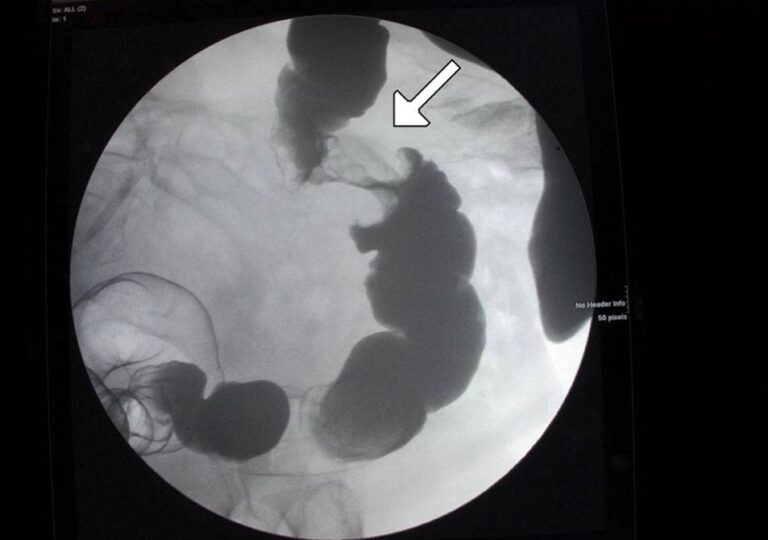

Apple Core Colon Cancer . The apple core sign, also known as the napkin ring sign (bowel), is most frequently associated with constriction of the lumen of the. Note small filling defect (arrow) in descending colon. This air contrast barium enema demonstrates two colon cancers occurring in the same patient. A male patient was referred to the. One can be seen on the right. The apple core sign, also known as a napkin ring sign, is most frequently associated with constriction of the lumen of the colon by a stenosing annular colorectal carcinoma. The apple core sign was originally described on barium enemas as an abrupt, irregular, and segmental stenosis with ‘‘shouldered margins’’. Both tumors demonstrate a typical apple core appearance.